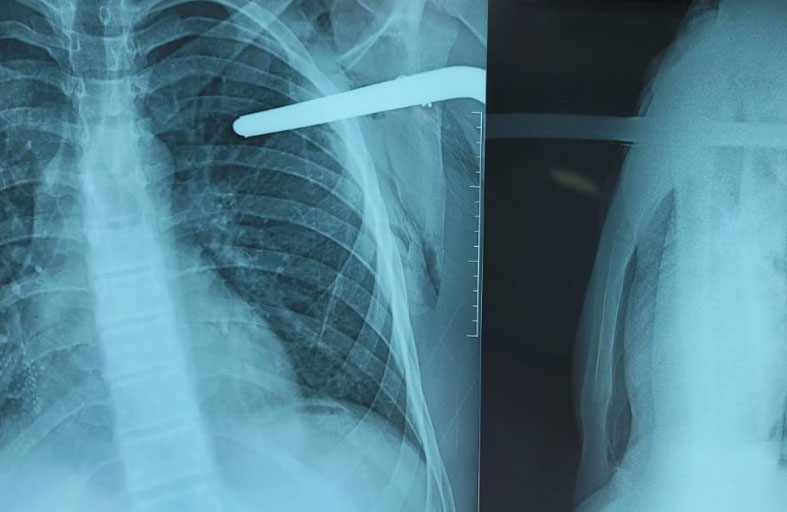

شهدت غرفة الطوارئ في مستشفى تركي مشاركة نادرة بين جراحين ورجال دفاع مدني؛ لإنقاذ مريض اخترق قضيب معدني طويل صدره من طرفين.

ووصل الرجل إلى المستشفى بإصابة خطيرة في موقع بناء بمحافظة "هاتاي" جنوبي تركيا، تسببت بدخول القضيب الحديدي من منطقة الصدر الأمامية وخروج طرفه الآخر من أعلى الخاصرة اليمنى.

ووجد الأطباء صعوبة في التعامل مع الحادثة بمفردهم، ما دفعهم لطلب فريق متخصص من الدفاع المدني لمشاركتهم العمل داخل غرفة الطوارئ لإخراج القضيب.

وأظهر مقطع فيديو عمل عناصر الطوارئ الذين استخدموا منشاراً كهربائياً لقص الحديد بعد توفير جدار حماية لجسم المصاب. وجرت كل تلك العملية بينما المصاب مستيقظ ويشاهد عملية قص القضيب الحديدي، فيما يحاول الفريق الطبي طمأنته. وقالت وسائل إعلام محلية، إن عمل عناصر الدفاع المدني استغرق نصف ساعة تقريباً، قبل أن ينسحبوا ويتركوا باقي المهمة للفريق الطبي. وأضافت أن الرجل تحسنت حالته بعد أربعة أيام من الحادثة، ونجاح عملية إخراج القضيب الحديدي من صدره، ويتعافى في المستشفى استعداداً للمغادرة.